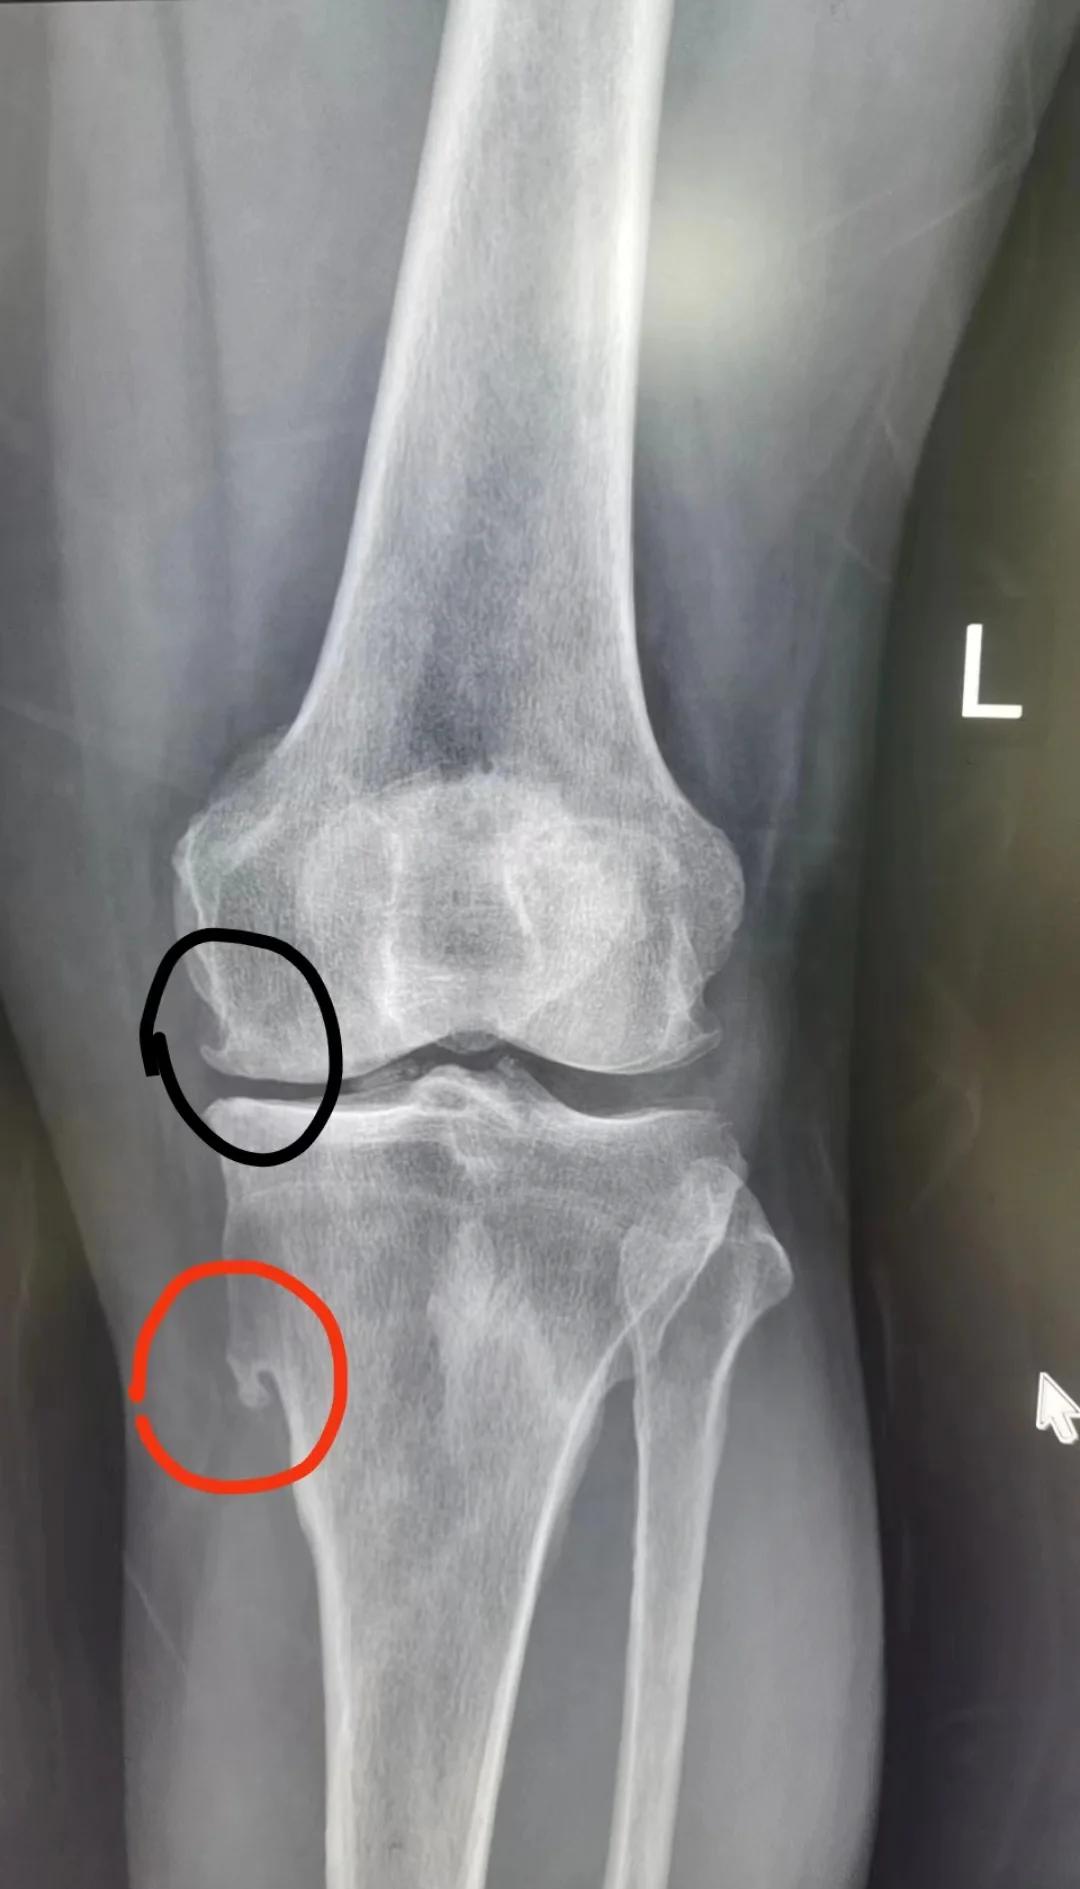

5、软骨瘤是起源于透明软骨的良性骨肿瘤,具体信息如下一分类及特点软骨瘤分为三类单发性内生性软骨瘤多见于青少年,好发于手足短管状骨,通常无明显症状,多因偶然发现无痛性肿块或轻微外伤后病理性骨折就诊多发性内生性软骨瘤包括Ollier病多发性软骨瘤伴骨骼发育畸形和Maffucci综合征多发性软骨瘤伴软组织血管瘤;软骨瘤的最佳手术时间需综合肿瘤大小部位生长速度及患者年龄等因素确定儿童患者手术时机需谨慎选择,因儿童骨骼处于发育阶段,过早手术可能影响骨骼正常生长一般建议在肿瘤停止生长后进行手术具体而言,肱骨近端和股骨远端的软骨瘤,建议在1214岁左右手术胫骨近端的软骨瘤,建议在1618岁左右;膝盖上长出硬硬的东西,可能由以下原因引起,需根据具体情况诊断和治疗1 骨软骨瘤骨软骨瘤是青少年及儿童常见的良性骨肿瘤,由软骨帽和骨性基底构成,多单发也可多发若位于膝关节附近,可触及硬质肿块多数无症状,但肿瘤较大时可能影响膝关节活动诊断需通过X光或CT检查,无症状的小肿瘤无需治疗。